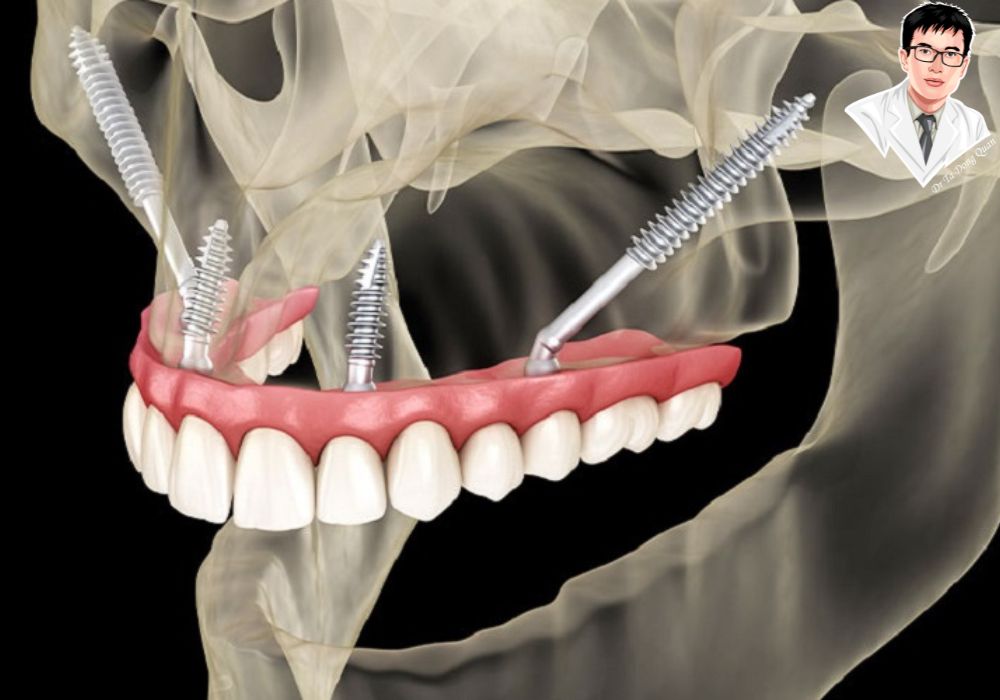

Implant xương gò má là trụ titanium dài, được đặt vào xương gò má – nơi chắc khỏe hơn xương hàm đã tiêu. Trụ này giúp nâng đỡ răng giả cố định, thay thế cho cả hàm trên nếu cần, mà không cần nâng xoang hay ghép xương.

Với người mất răng lâu năm và tiêu xương nặng, việc trồng răng luôn là một thử thách vì không còn đủ nền xương hàm để đặt trụ. Implant thường hoặc All-on-4 thường thất bại trong những trường hợp này. Tuy nhiên, implant xương gò má được thiết kế đặc biệt để khắc phục điều đó: trụ dài được neo vào xương gò má – nơi có mật độ xương chắc khỏe nhất vùng mặt, giúp cố định chắc chắn mà không cần ghép xương hay nâng xoang.

Phục hình răng toàn hàm bằng implant Zygoma, cấy nghiêng và dài để bám vào xương gò má.